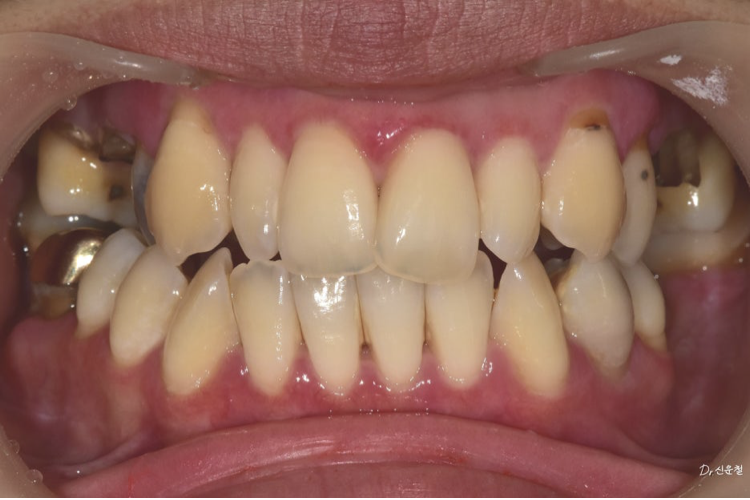

실제로 내원하신 30대 여성 환자분도

“아프진 않아요.”라고 말씀하셨습니다.

촬영일 250327

하지만 정밀 검진 결과, 깊게 진행된 사랑니 충치 뿌리만 남은 치아

잇몸뼈가 녹아 흔들리는 어금니 가 확인되었습니다.

통증이 없었던 것뿐,

문제는 이미 상당히 진행된 상태였습니다.

앞니만이 아니라 ‘웃는 전체’를 보셔야 합니다

웃을 때는 앞니만 보이지 않습니다.

어금니까지 함께 보입니다.

앞니 배열만이 아니라 어금니 충치, 보철 색감, 잇몸 라인까지

전체적인 밸런스를 함께 봐야 합니다.